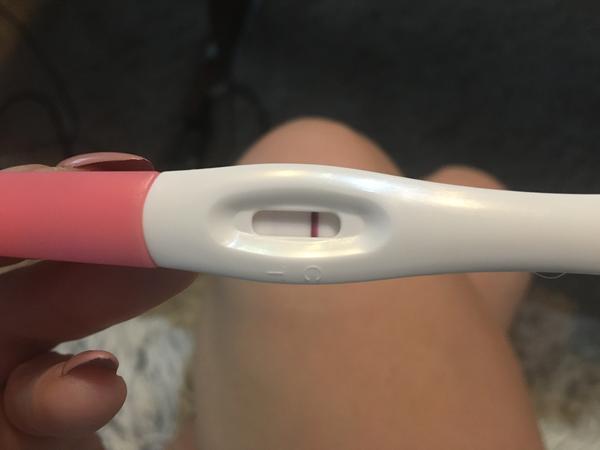

Duch na teste

ahojte babule, mam taku otazku...mate skusenost ze pocas 3 dni vam nesilnela druha ciarka na teste ale bola rovnaka???ako duch????